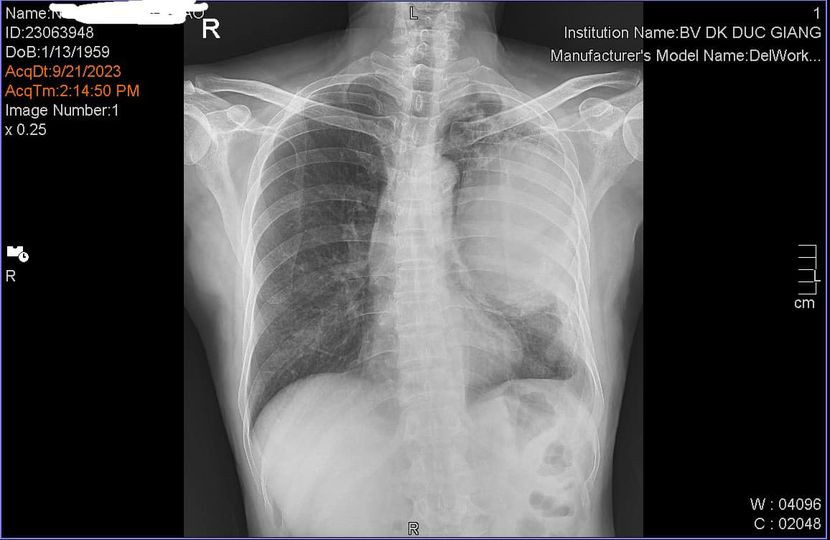

Bệnh nhân 64 tuổi có địa chỉ ở Long Biên (Hà Nội) vào Bệnh viện Đa khoa Đức Giang khám vào cuối tháng 9. Ông làm nghề xây dựng, thâm niên hút thuốc lá, thuốc lào trên 40 năm. Nói với bác sĩ, ông cho biết ngoài các dấu hiệu trên, ông không đau ngực, không khó thở.

Sau khi phát hiện u ở phổi trái, ông được nhập viện điều trị tại khoa Ung bướu. Tại đây, các bác sĩ chỉ định khám tầm soát như nội soi dạ dày, đại tràng, chụp cắt lớp sọ não, cắt lớp vi tính phổi, sinh thiết xuyên thành, nội soi khí phế quản.

Ngoài việc phát hiện tế bào lạ nghi ngờ ác tính, bác sĩ xác định khối u xâm lấn làm tắc hoàn toàn phế quản gốc bên trái và chiếm gần hết nhu mô phổi trái.